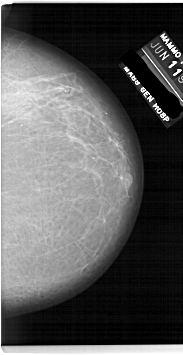

A_1920_1.LEFT_MLO

LEFT_MLO LINES 6751 PIXELS_PER_LINE 3946 BITS_PER_PIXEL 12 RESOLUTION 43.5 OVERLAY

FILE: A_1920_1.LEFT_MLO.OVERLAY

TOTAL_ABNORMALITIES 1

ABNORMALITY 1

LESION_TYPE MASS SHAPE OVAL MARGINS OBSCURED

ASSESSMENT 3

SUBTLETY 4

PATHOLOGY BENIGN

TOTAL_OUTLINES 1

BOUNDARY